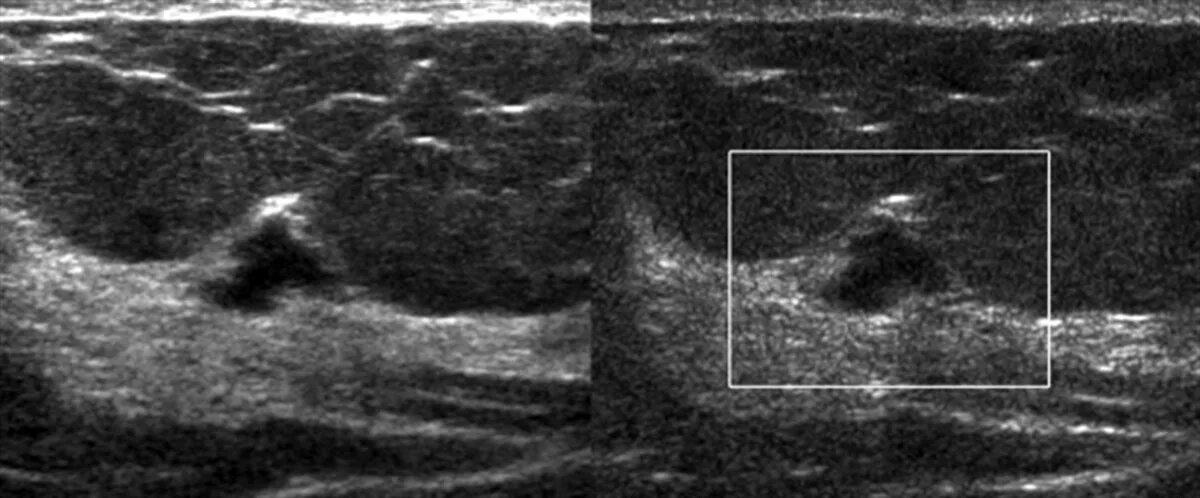

Как выглядит фиброаденома молочной железы